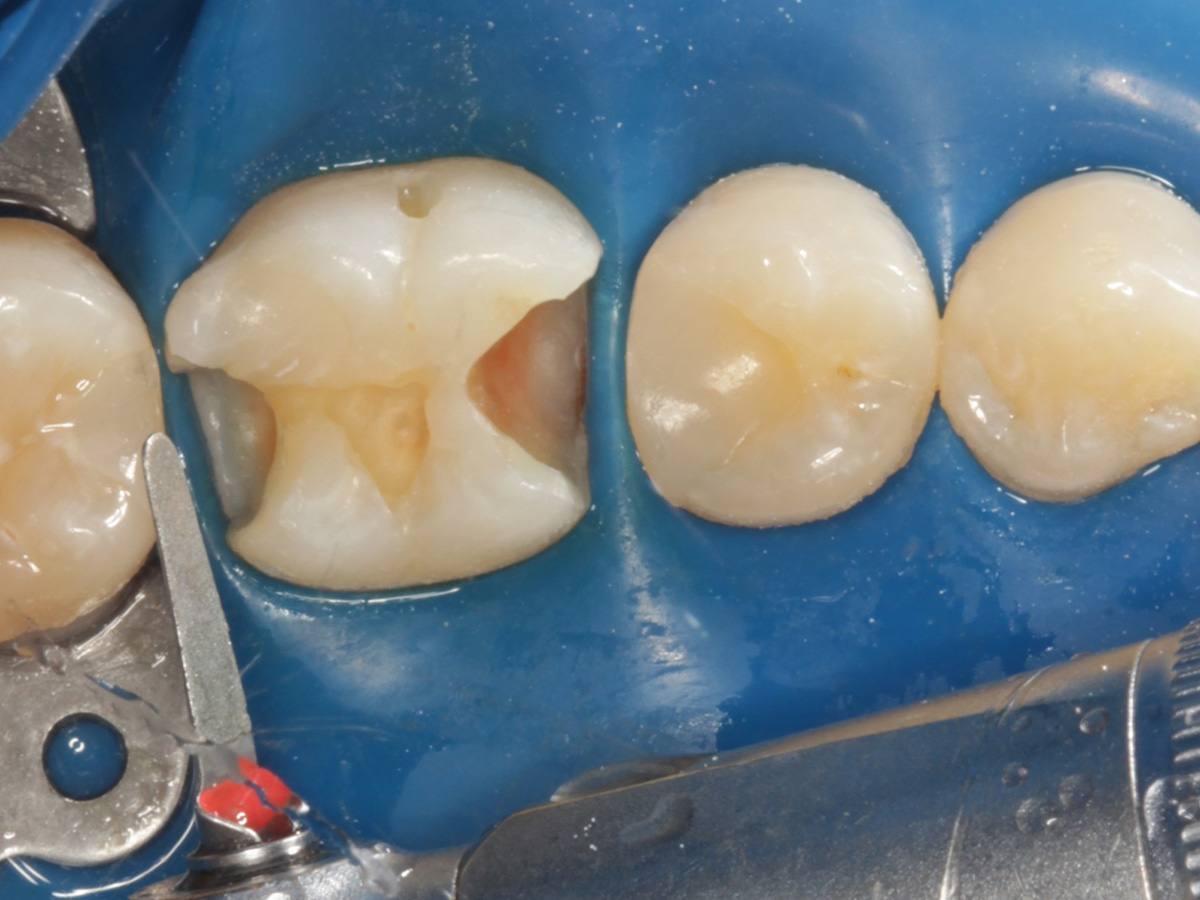

Abbildung 10

Height Indicator vor Auswahl der passenden Evolve Matrize distal

Abbildung 11

Height Indicator vor Auswahl der passenden Evolve Matrize mesial

Abbildung 12

Applikation der Matrizen: Evolve Blau Molar 5 mm distal und 6 mm mesial